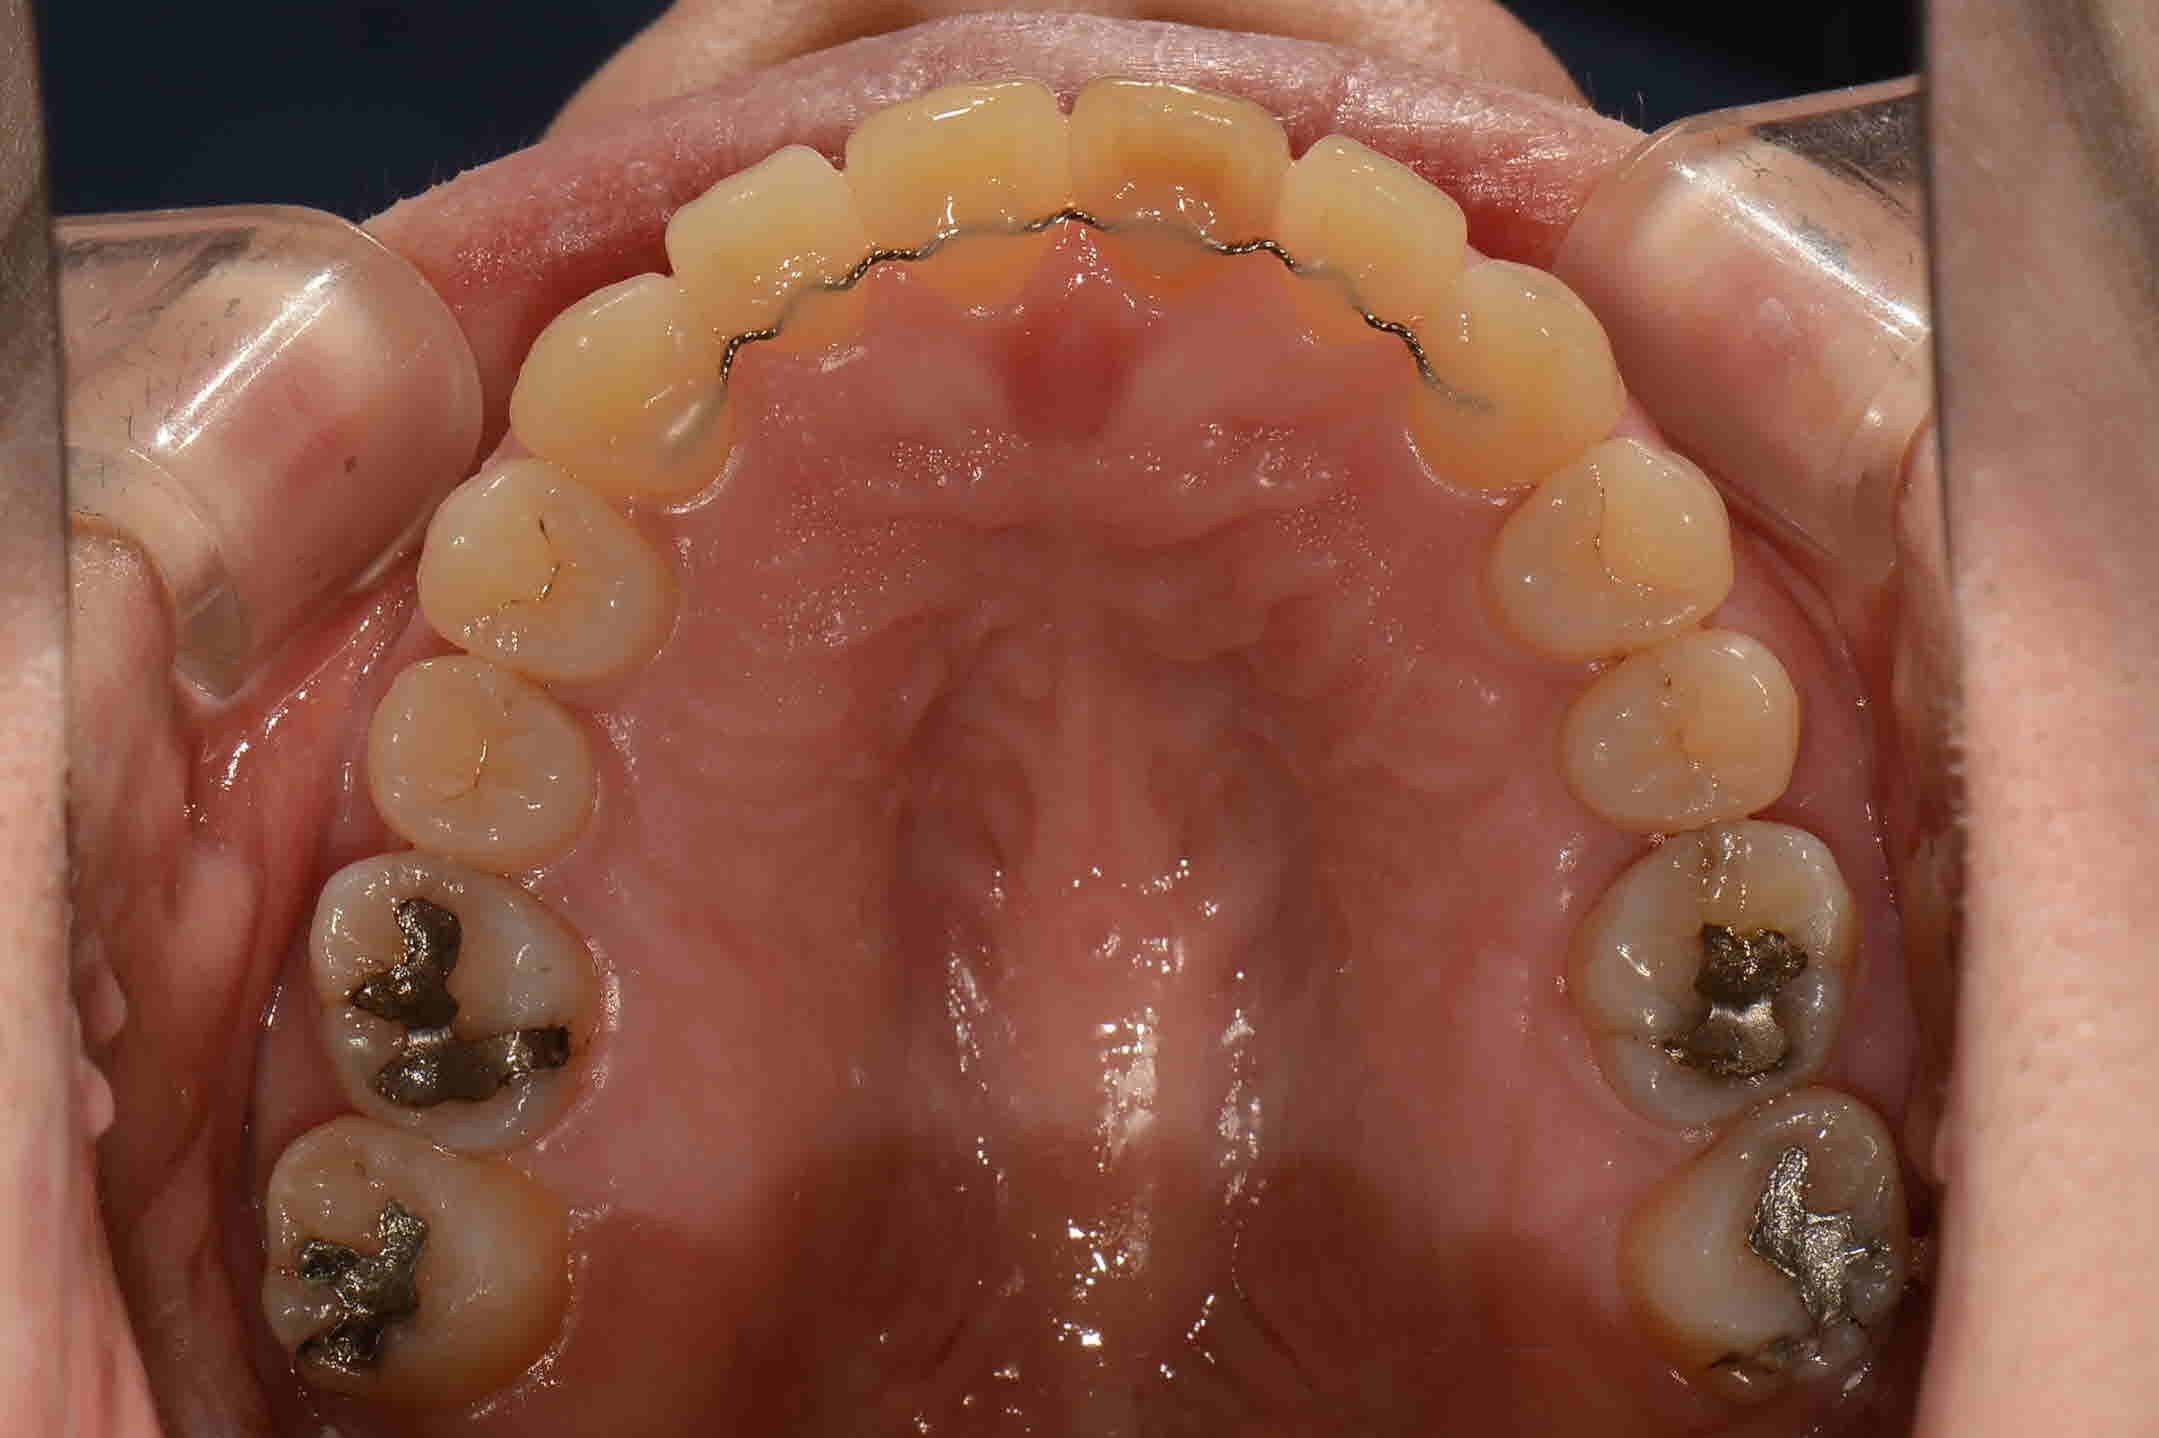

교정시작 교합면

-

2017년 05월 교합면

2017년 8월 교합면

2017년 10월 교합면

2018 년 1월 교합면

교정완료 교합면